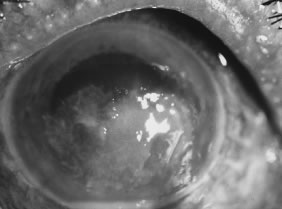

Advanced, severe filamentous fungal or yeast keratitis is indistinguishable from keratitis caused by virulent bacteria such as Staphylococcus aureus or Pseudomonas aeruginosa. The area of epithelial and stromal ulceration is large. Dense, opaque, homogenous, yellow-white stromal necrosis develop and is surrounded by confluent cellular infiltrate and full-thickness stromal edema (Figs. 19, 20, 21). Hyphal elements may penetrate Descemet's membrane and endothelium and be visualized in the anterior chamber. Fibrinous material accumulates over the endothelium, anterior chamber angle, and iris. Pain is typically severe. Secondary ocular hypertension may ensue. Progressive stromal necrosis leads to corneal perforation and, rarely, consecutive endophthalmitis.

Fig. 19. F. solani keratitis in an 81-year-old man, 3 weeks following corneal injury with a stick. Empirical antibacterial therapy for presumed bacterial keratitis. Note the area of dense, white suppurative stromal keratitis and hypopyon. Failure of antifungal therapy required therapeutic penetrating keratoplasty.

Fig. 20. C. albicans in a woman after chronic administration of proparacaine hydrochloride drops. A. Full illumination. B. Slit illumination. Dense, homogenous suppuration is noted.

Fig. 21. C. parapsilosis keratitis in a blind eye after orbital trauma and exposure. Note the liquefactive necrosis and purulent exudates.